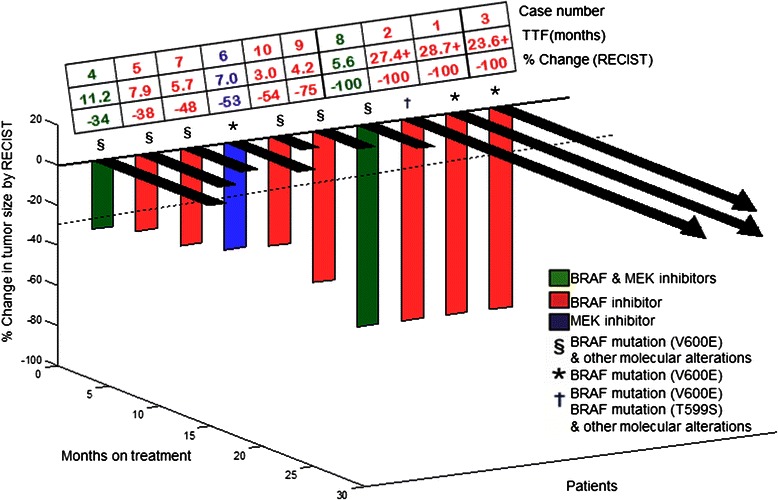

Nine of ten patients with BRAF mutations were treated with BRAF inhibitors, either as a single agent (7 patients) or in combination with a MEK inhibitor (2 patients). The remaining one patient was treated with a single-agent MEK inhibitor. The clinical trials are summarized in Additional file 2. Four of ten patients (40%) had a CR, three of which are ongoing for about two years or longer (TTF = 5.6, 23.6+, 27.4+, and 28.7+ months). Six patients (60%) attained a PR (TTF = 3.0, 4.2, 5.7, 7.0, 7.9, and 11.2 months) (Figures 1 and 2).

Figure 1.

3-D waterfall plot. Best response by RECIST, of ten patients with BRAF-positive melanoma. Time to treatment failure in months is represented by solid lines and the arrow indicates that the patient was still on study when the data was censored.